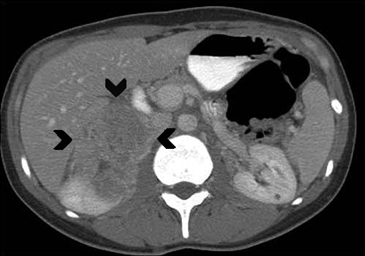

La presencia de lípidos intracelulares disminuye la densidad de la lesión debido a que estos son menos densos que el agua. El primer estudio en reportar la utilidad de la densitometría por TC en la diferenciación de una lesión suprarrenal benigna de una maligna fue el realizado por Lee et al6, utilizando la medición del coeficiente de atenuación o densidad de la lesión expresada en unidades Hounsfield (UH), en una TC no contrastada, demostrando que el coeficiente de atenuación promedio de los adenomas (2,2 UH) fue significativamente menor que la de las lesiones no adenomas (28,9 UH). Utilizando un punto de corte de 0 UH la sensibilidad de la TC no contrastada en la caracterización de un adenoma es cercana a un 47%, con una especificidad de aproximadamente 100% (Figura 9 a y b). Sin embargo, estudios posteriores7 han corroborado que al utilizar un punto de corte de 10 UH, la sensibilidad asciende a un 71%, y la especificidad se mantiene en prácticamente 98%, por lo que este umbral de densidad es el más utilizado en la actualidad. Es importante enfatizar que para una adecuada medición de la densidad, la región de interés (ROI) no debe incluir áreas de necrosis ni de hemorragia, y debe abarcar al menos la mitad o dos tercios de la lesión, para evitar el artefacto por ruido y el efecto de volumen parcial con el tejido adiposo adyacente (Figura 10).

A

B

Figura 10. Adenoma suprarrenal derecho. Lesión suprarrenal derecha, cuya densidad es consistente con un adenoma típico. En la imagen se demuestra una adecuada medición de la densidad lesional, con una región de interés (ROI) que abarca al menos dos tercios de ésta.